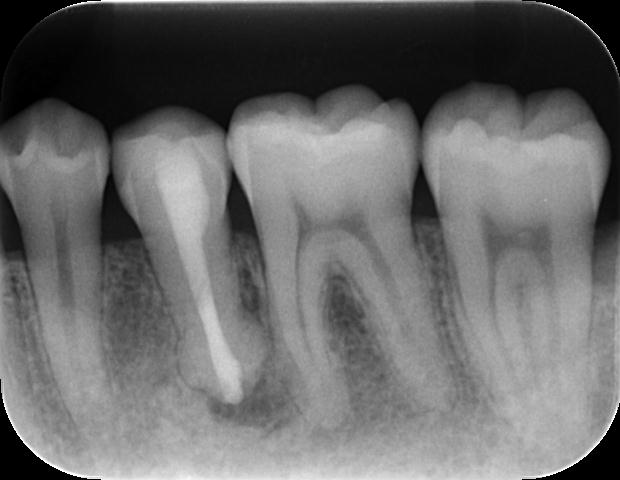

時系列でレントゲン写真をご覧いただきます。

治療前

根管充填後

外科的歯内療法後 術後1年